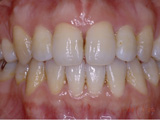

症例1:乱杭歯「歯並びが乱れている」

治療後